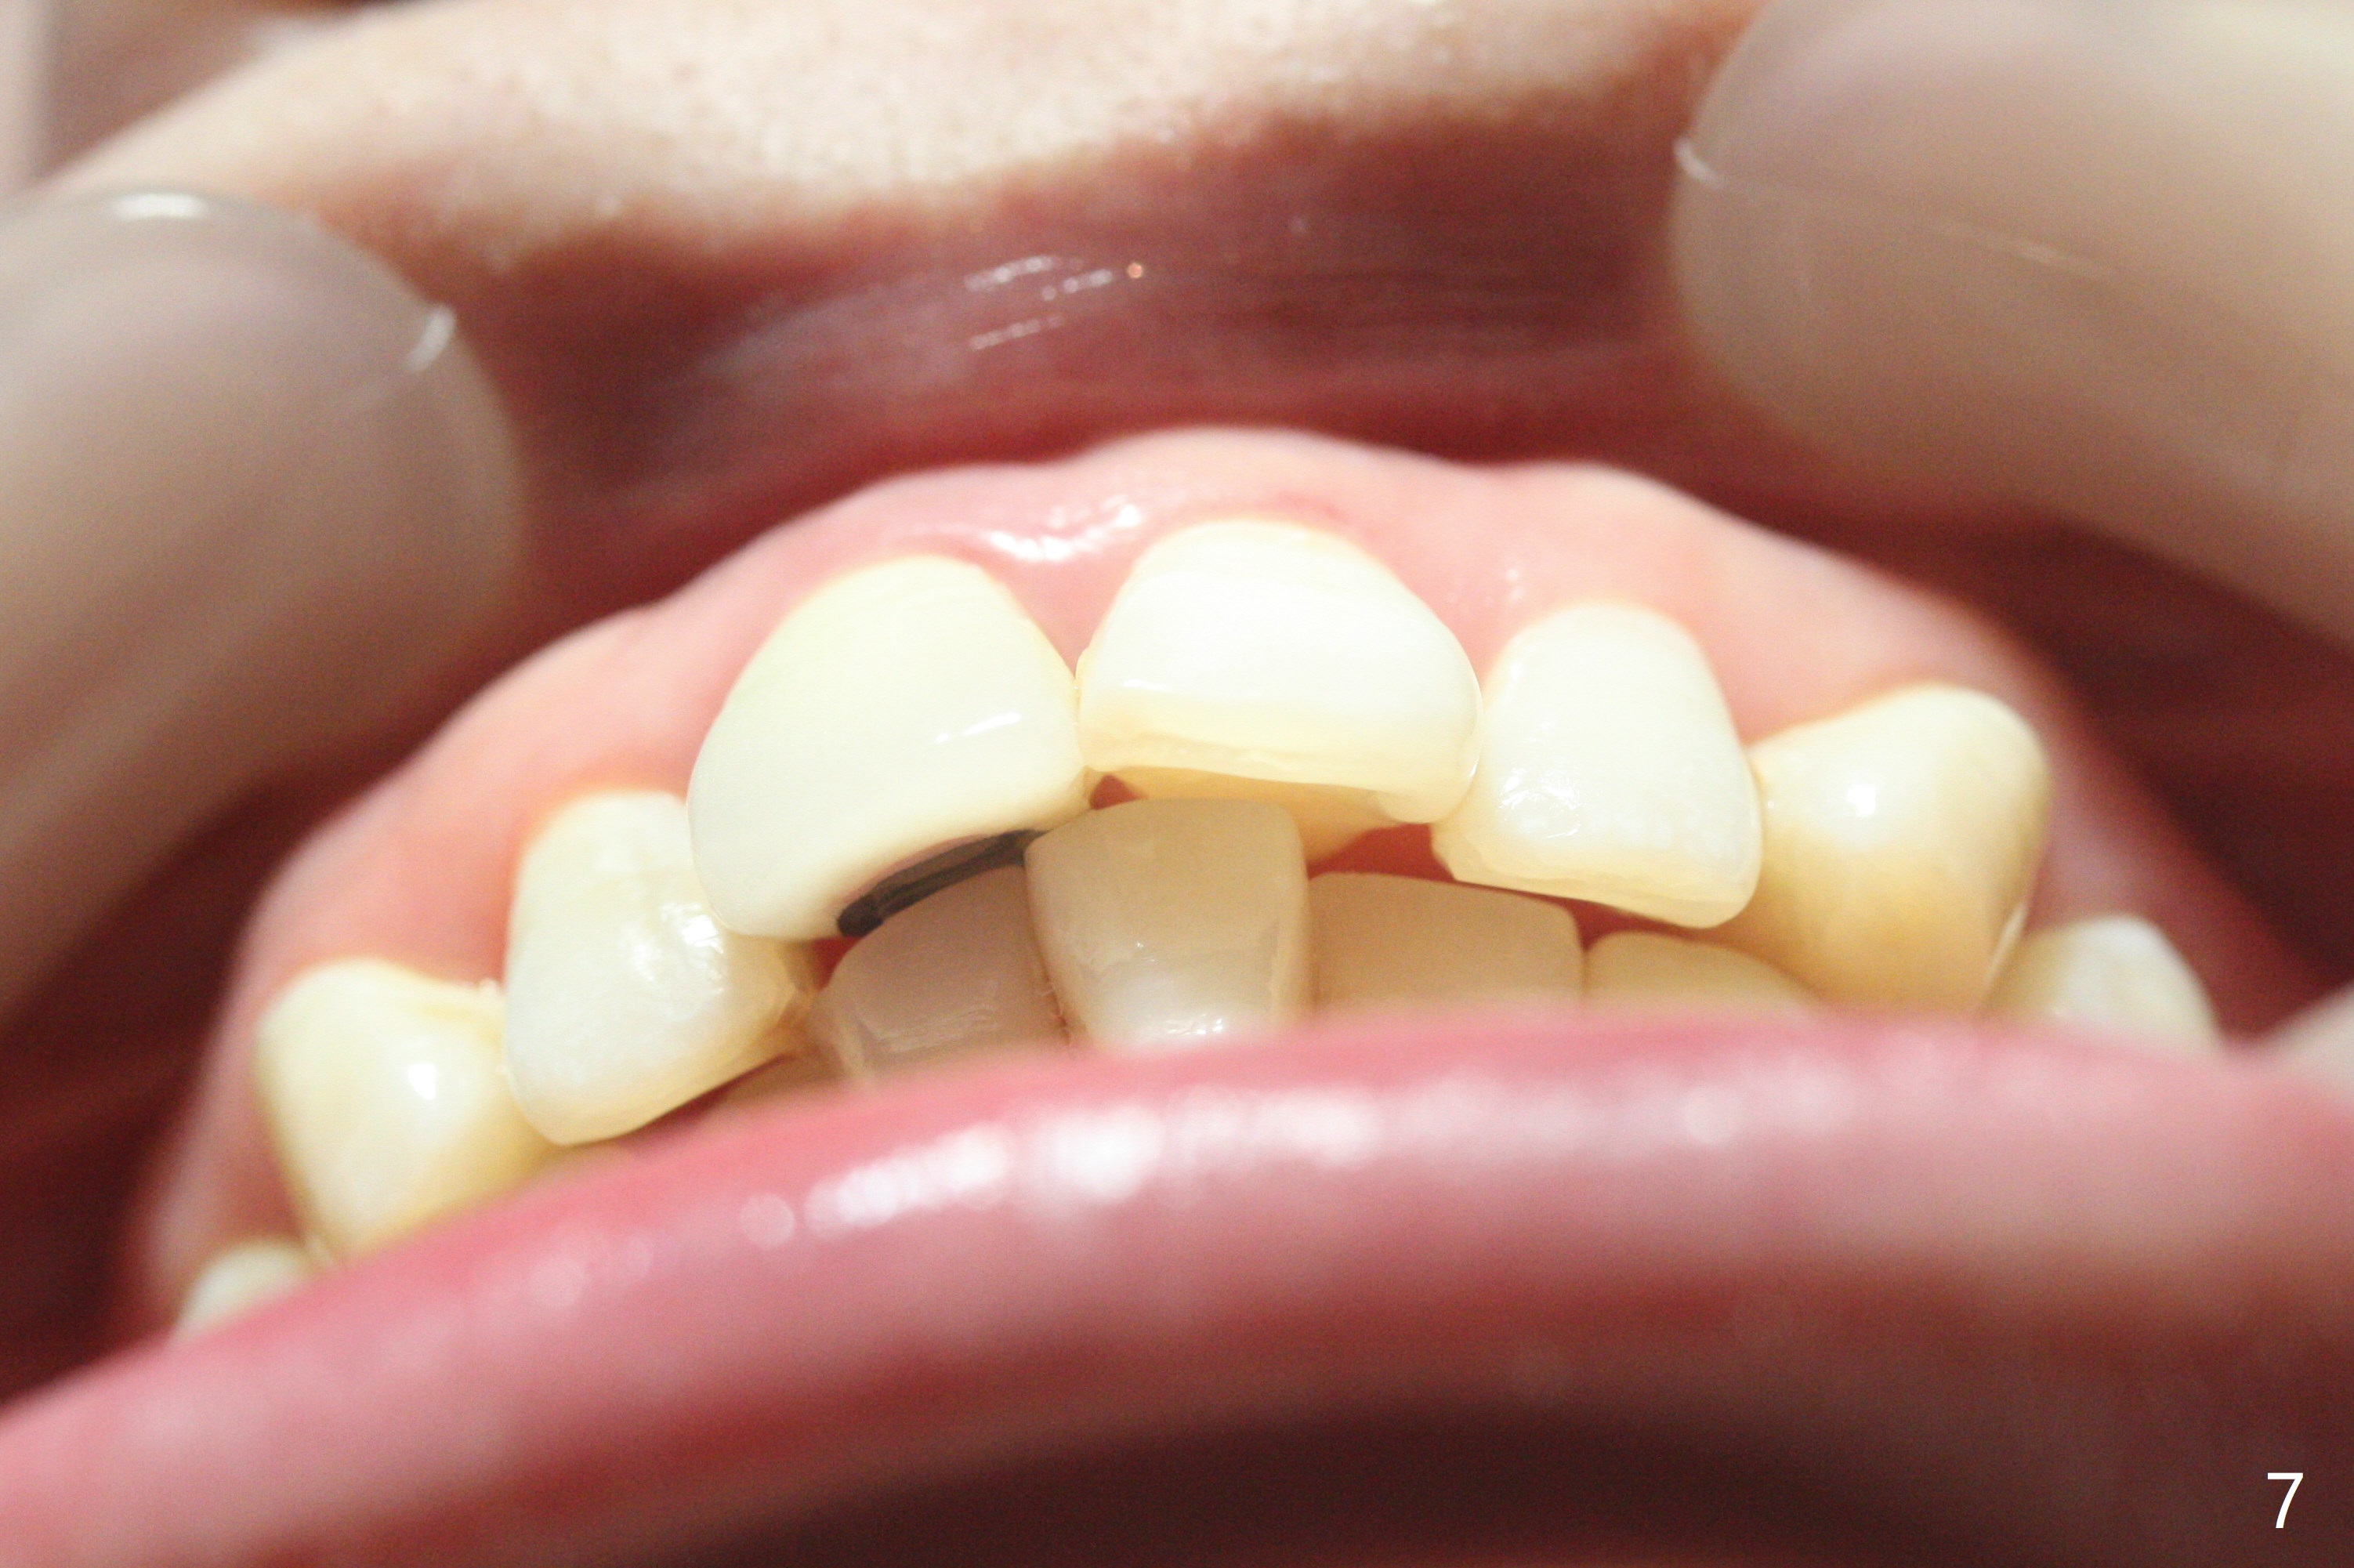

31岁女面部还匀称(图一,二,四,五),但是二类错𬌗严重(图三,六至十),应尽早做二类牵引。压低左上6是 头等大事。磨牙间隙不容易产生,为了避免矫正后磨牙间隙问题,不放置磨牙bands,在右上,右下6,左上6,7放置矫正器,再次使用12niti弓丝。